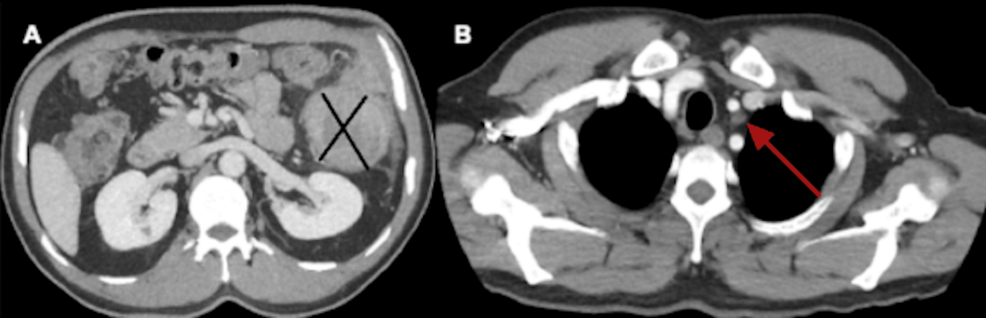

| Abdominal CT (contrast‑enhanced) | Multiphase CT abdomen/pelvis | Segmental wall thickening of the sigmoid colon,pericolic fat stranding,enlarged mesenteric lymph nodes (short axis ≈ 12 mm) | Detects mass effect and regional nodal involvement; aligns with CT staging criteria [3] |